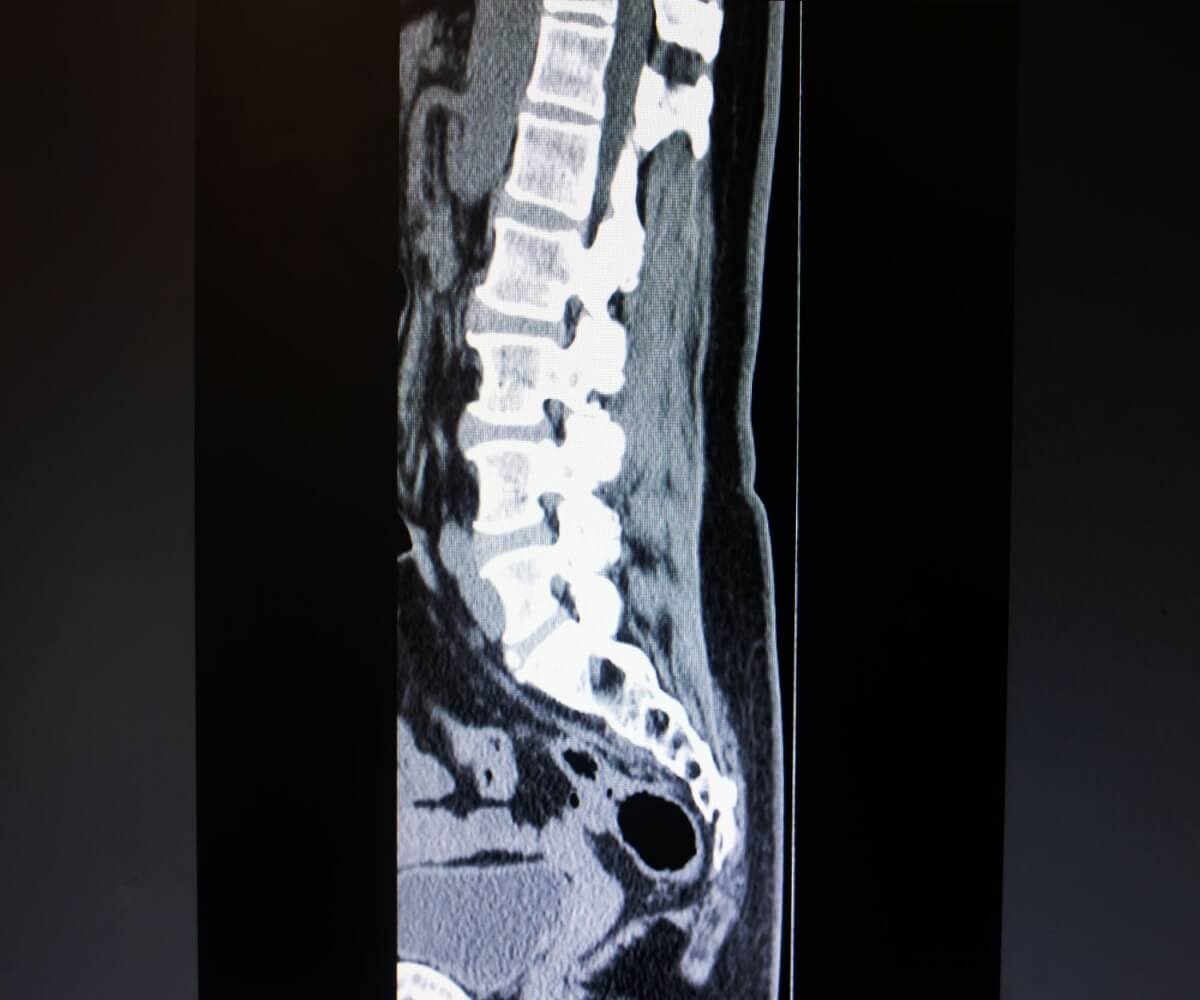

추간판이라고 불리는 디스크는 척추 사이에 존재하면서 외부의 충격 및 압력을 흡수하는 역할을 합니다. 이러한 디스크 덕분에 우리의 척추, 신경, 근육, 뼈에 오는 충격과 진동이 상당 부분 완화되는 효과를 가집니다. 정상적인 디스크는 MRI 상 높이가 1cm 이상이며 디스크 안에 물이 많이 차있어 충격 완화에 높은 효율을 보여줍니다. 하지만 퇴행성 디스크가 진행되면 디스크 안에 물이 빠져 MRI 상에서 검은색으로 보이게 되며, 이후에는 높이까지 줄어들어 충격 완화의 기능을 거의 하지 못하게 됩니다. 즉, 퇴행성 디스크는 잘못된 습관이나 강한 압력의 반복 등의 좋지 않은 습관으로 디스크가 퇴행되어 늙어버린 것을 의미합니다. 퇴행성 허리디스크는 누구든지 노화함에 따라 발생할 수 있는 질환입니다.